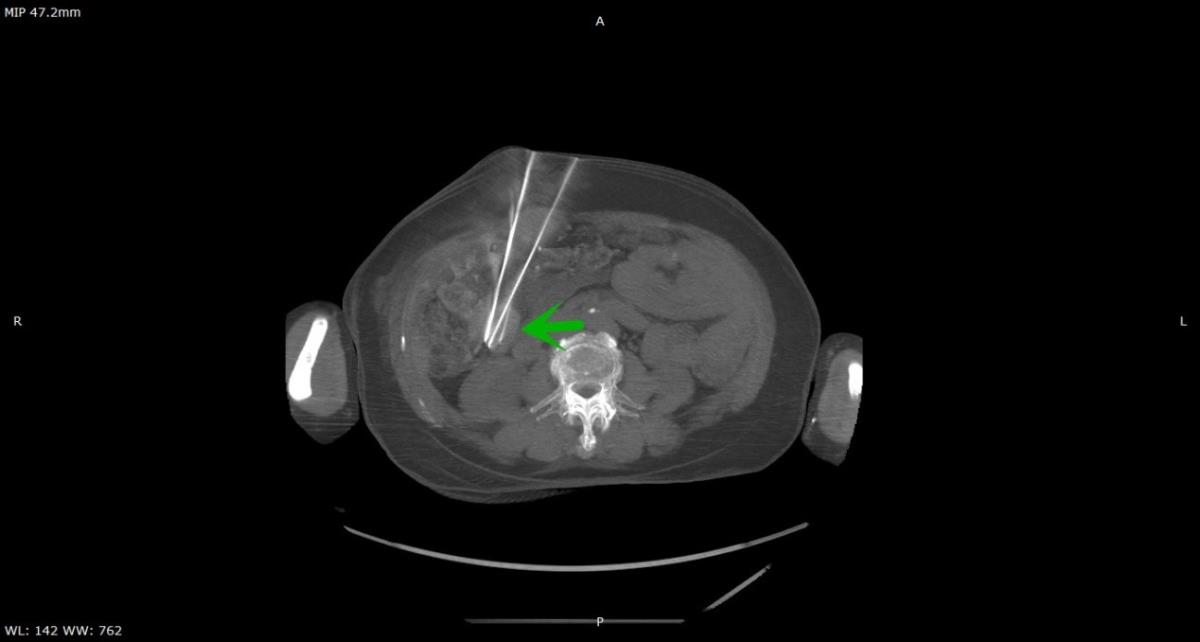

病例二:患者范某,女,82岁,卵巢癌腹部多发转移瘤行粒子植入手术。转移瘤大小约3cmx4cmx3.5cm,拟分布3根穿刺针,植入12颗粒子。转移瘤贴近肾脏边缘,位于肾动脉旁,穿刺位置深度达18cm,进针路径中需要避开腹部肠管,手术风险非常高。术中通过导航机器人计划系统一次布置3针,均采用一步进针方式完成,通过机器人验证系统可以看到进针全部到达靶区,术后验证与计划处置完全一致,穿刺位置非常理想,行粒子植入手术。术中CT扫描3次,计划处置时间13min,术后未发生并发症。

穿刺结果与计划完全一致